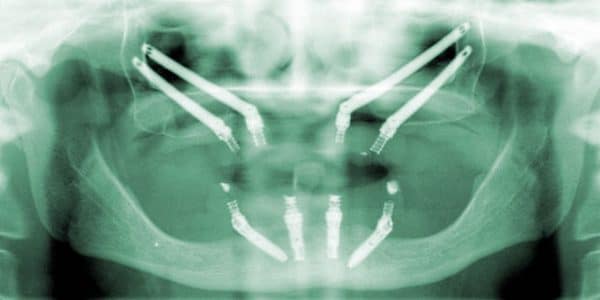

These implants are called All-on-4® Zygomatic implants and are anchored into the cheek bone, providing an alternative to grafting procedures in the upper jaw.

In some cases the upper jaw may be very deficient in bone even in the anterior region. For these cases double zygoma implants may be inserted into both sides of the available check bone to support a full upper set of replacement teeth.